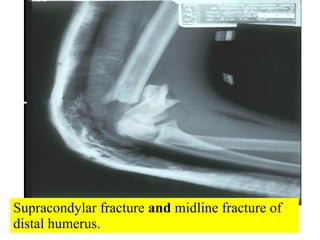

Supracondylar fracture  and  midline fracture of distal humerus.